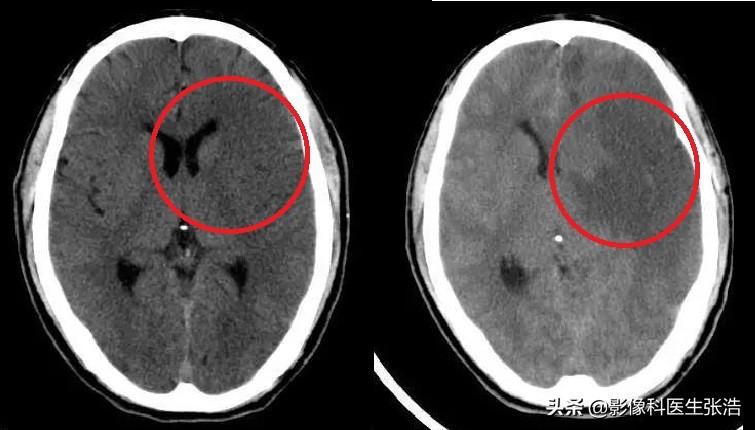

腦梗的診斷

腦梗的診斷主要依據(jù)患者的病史、體格檢查和影像學(xué)檢查,醫(yī)生會(huì)根據(jù)患者的癥狀、體征以及可能的病因進(jìn)行初步判斷,并結(jié)合頭顱CT、MRI等影像學(xué)檢查來確診。